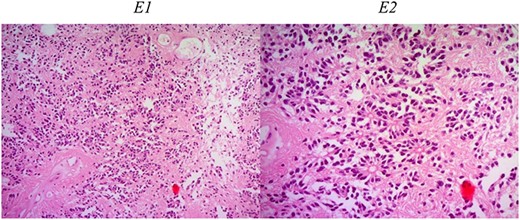

After surgery, the tumor at C5–C7 showed meningothelial meningioma (Fig. 3). The second tumor in the spine at C2–C4 was ependymoma (Fig. 4). Tumor in the brain showed rhabdoid meningioma (Fig. 5).

Histologic description of ependymoma component. E1 (H&E ×50): moderately cellular with round/oval nuclei having discrete interface with surrounding parenchyma. E2 (H&E ×200): monomorphic cells with salt and pepper chromatin. Key histological features are perivascular pseudorosettes and ependymal rosettes.